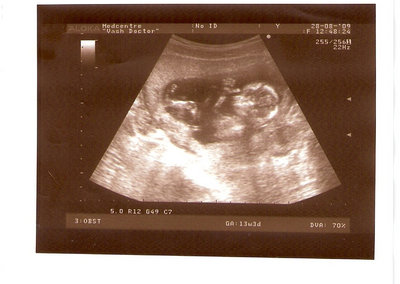

СЫН

2.jpg [ 110.14 КБ | Просмотров: 2458 ]

13 НЕД И 5 ДНЕЙ

3.jpg [ 96.81 КБ | Просмотров: 2456 ]

Nikisa писал(а): Foto prosto chudesnoe. A na kakom sroke uznali, chto sin.............. НА 13 НЕДЕЛЯХ.КАК РАЗ ВОТ В ЭТО узи, ОНО УМЕНЯ ВТОРОЕ БЫЛО. ЭТО КОНЕЧНО МАЛЕНЬКИЙ СРОК ДЛЯ ОПРЕДЕЛЕНИЯ ПОЛА. НО Я ПОПРОСИЛА ВРАЧА(ЭТО КТСТАТИВ РОССИИ БЫЛО) ХОТЯ БЫ ПРЕДПОЛОЖИТЬ. ЕЙ ВСЁ ТАКИ УДАЛОСЬ РАССМОТРЕТЬ.НУ ВООБЩЕМ ЧЕРЕЗ НЕСКОЛЬ ДНЕЙ ПОЙДУ К ВРАЧУ, УЖЕ АМЕРЕКАНСКОМУ И УЗНАЮ ТОЧНО. К ТОМУ ВРЕМЕНИ У МЕНЯ БУДЕТ СРОК 18 НЕДЕЛЬ. ХОТЕЛОСЬ БЫ ПОСМОТРЕТЬ НА ДРУГИЕ ФОТО НА ЭТОМ СРОКЕ ИЛИ БОЛЬШЕ. ТАК ЧТО ВЫКЛАДЫВАЙТЕ, ЕСЛИ НЕ ЖАЛКО!